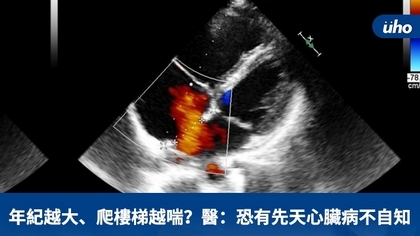

年紀越大、爬樓梯越喘?醫:恐有先天心臟病不自知

(優活健康網新聞部/綜合報導)一名20幾歲年輕女性,近來爬樓梯感覺會喘,經過健康檢查發現有心雜音狀況;另一位60歲女士也有同樣情況,平時活動偶爾會喘,健檢之後發現心臟擴大。這2個案例至心臟科門診檢查後,經醫師診斷是「心房中膈缺損」需手術。 心臟血液跑到肺動脈致右心室衰竭新竹台大分院小兒部小兒心臟科醫師傅俊閔說明,「心房中膈缺損」是一種先天性心臟病,正常人左心房與右心房互不連通,由心房中膈隔開,若是心房中膈有破洞就稱為「心房中膈缺損」。傅俊閔解釋,心房中膈缺損會造成血液經此破洞從左心房流到右心房、右心室再到肺動脈,導致右心室與肺動脈擴大,因而會產生活動耐受性降低、容易喘等右心室衰竭症狀,嚴重甚至可能導致肺動脈高血壓等嚴重併發症,需要積極治療。 年輕時沒有明顯不適  健檢時才發現問題多數患者在年輕時可能沒有明顯不適,或者健檢時僅發現輕微心雜音,隨著年齡增長才出現較明顯症狀。因此有些人到成年,甚至中老年後才被診斷出有心房中膈缺損。傅俊閔表示,心房中膈缺損根據缺損所在之解剖位置分類,其中第二型心房中膈缺損,可利用心導管手術將其關閉,效果好且恢復快,只有腹股溝會有個小傷口。其他型的心房中膈缺損則因為破洞位置較不適合關閉器放置,仍有可能需要傳統手術治療。 新竹台大分院小兒心臟科團隊過去幾年與該院麻醉科合作,已陸續成功完成多例「經心導管心房中膈缺損關閉手術」和「開放性動脈導管關閉手術」,前述2名病人也在傅俊閔安排心導管手術後,順利關閉心房中膈缺損,術後皆恢復良好,目前持續於門診追蹤。